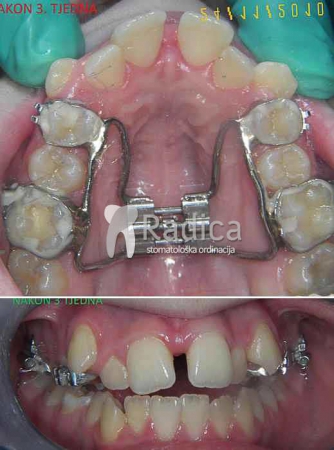

Hyrax se pomoću prstene fiksira na prve trajne molare i prve premolare. Vijak se okreće svaki dan i već nakon par dana se vidi učinak jer se pojavljuje razmak između sjekutića. Nakon dva tjedna se vijak blokira i aparat ostaje u ustima najmanje sljedećih 4-6 mjeseci. Fiksni aparat se obično stavi nakon tri mjeseca. Hyrax ima najbolji efekt u vrijeme mješovite denticije – najčešće između 9-12 godine.

U sljedećim galerijama možete vidjeti primjere upotrebe Hyraxa:

1. primjer